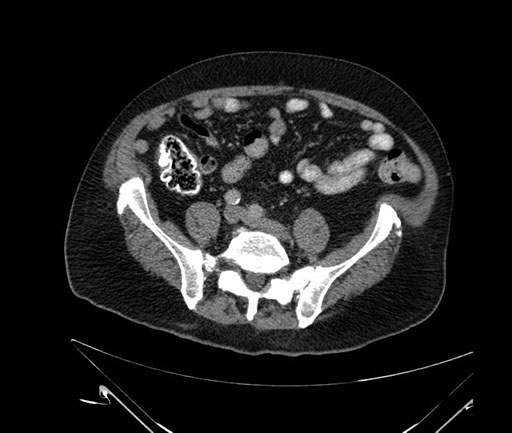

Axial - stented